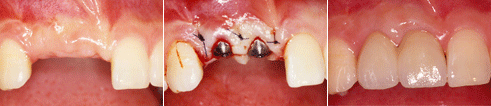

상실된 앞니부위에서 1회법으로 임플란트를 식립하고 회복한 증례

상실된 두 개의 앞니를 2개의 임플란트를 식립하여 회복한 증례

상한 앞니를 발거하고 즉시 임플란트를 식립하여 회복한 증례 임플란트 식립을 위한 골 증대술